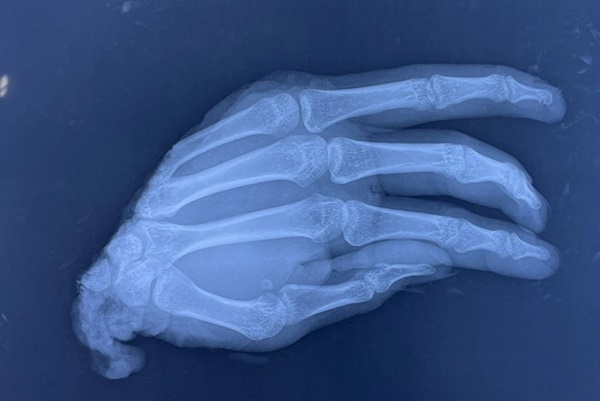

Nam thanh niên bị máy dập ở công xưởng làm đứt lìa hoàn toàn bàn tay phải (Ảnh: BV).

Phần đứt lìa của bệnh nhân bị dập đầu dưới xương quay. Trong khi đó, mạch máu thần kinh và gân bị dập lóc 1 đoạn, đã bị máy nghiền nát. Ekip phẫu thuật đã tiến hành cắt ngắn xương trụ để tạo hình cổ tay tương đối ổn định, sau đó ưu tiên ghép vi phẫu động mạch và tĩnh mạch để cứu bàn tay.